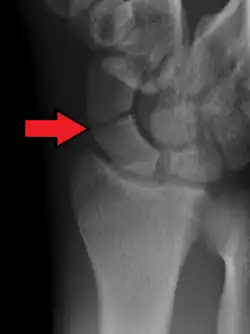

A more obvious scaphoid fracture on a scaphoid view X ray

Scaphoid fractures are often diagnosed using plain radiographs and multiple views are obtained as standard.[9] However, not all fractures are apparent initially.[7] In 1/4 of cases, the clinical examination suggests a fracture, but the X-ray does not show it, even though there is indeed a fracture.[10] Therefore, people with tenderness over the scaphoid (those who exhibit pain to pressure in the anatomic snuff box) are often splinted in a thumb spica for 7–10 days at which point a second set of X-rays is taken.[7] If a minimally displaced fracture was present initially, healing will now be apparent. Even then a fracture may not be apparent. A CT Scan can then be used to evaluate the scaphoid with greater resolution. The use of MRI, if available, is preferred over CT and can give one an immediate diagnosis.[11] Bone scintigraphy is also an effective method for diagnosis fracture which do not appear on Xray.[12]